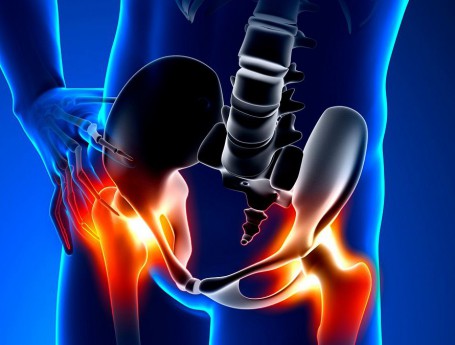

Hip Pain

Hip Surgery

Hip